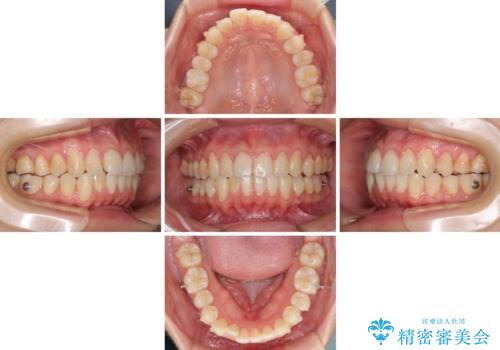

- 上下前歯のデコボコを気にして来院された患者様です。

インビザラインによる上下歯列の側方拡大と後方移動、IPR(歯と歯の間を削る)にるスペースの獲得により歯列を整えることとしました。

1日22時間の装着時間をしっかり守ってくださったので、予定していた1年よりも早く治療を終えることができました。

インビザライン矯正特有の奥歯がしっかりと咬合しない感覚も改善され、大変満足していただきました。